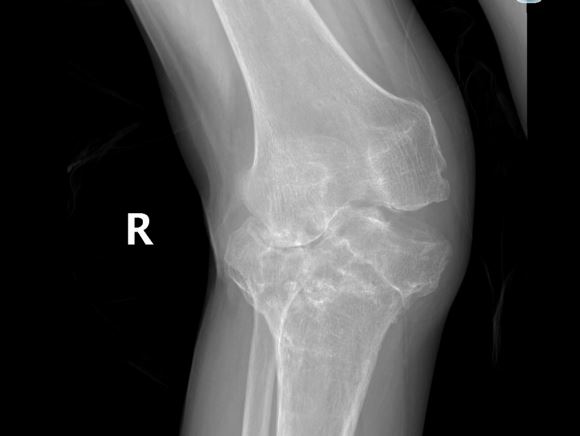

58岁的尤大叔是晋江内坑人,9年前因外伤导致右侧胫骨近端骨折,在外院进行手术治疗。但术后恢复欠佳,尤大叔行走状况逐渐受限,右膝关节严重外翻,因经济原因一直未进行系统治疗,生活、工作上带来的不便让他苦不堪言。

▲严重外翻畸形

▲术前影像